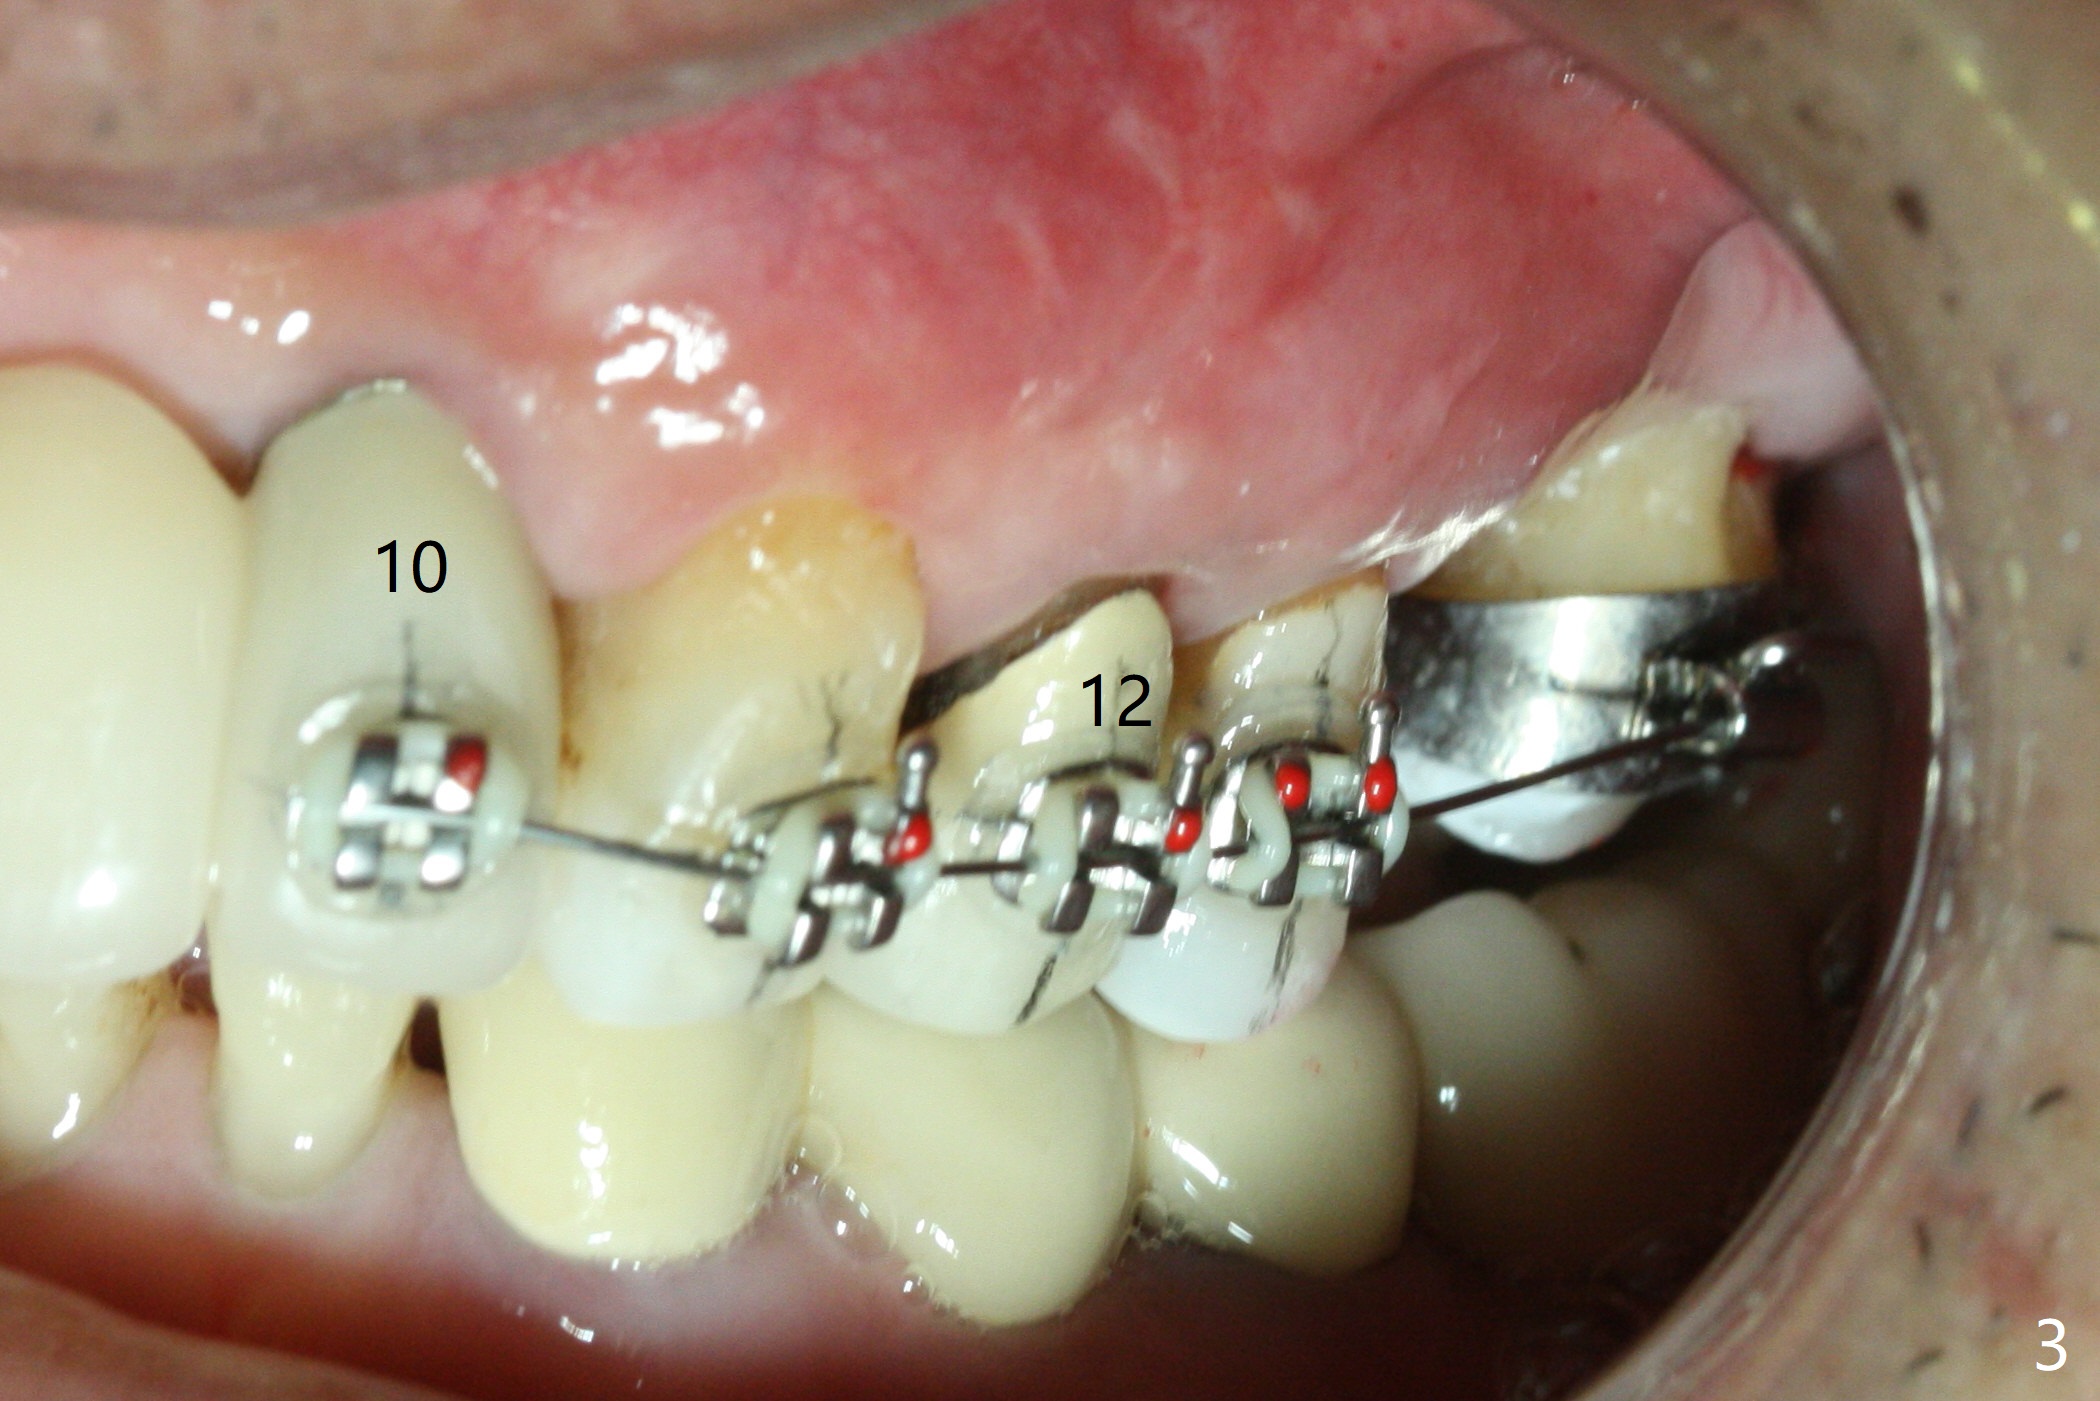

A 64-year-old man has multiple restorations. The tooth #2 seems to have root resorption. The tooth #27 has recently finished RCT. It appears necessary to establish sound occlusion on the left side by placing an implant at #14. First at all, the mesially tilted tooth #15 needs to be uprighted (Fig.2). The implant crown at #10 will be used as an anterior anchorage, since the three teeth (#11-13) are usually not strong enough to distalize the 2nd molar. To prevent debracketing at #10, a diamond bur will be used to roughen the crown surface and new bonding agent is applied. The second easily debracketing spot is #12 (crown), which could be used bicuspid band. The 3rd option to reduce debracketing is not to use rectangular wire initially. When the space at #14 increases to 8 mm mesiodistally, an implant will be placed. Once the implant is osteointegrated, a band is applied. From that point on, a rectangular wire could be used. If debracketing occurs at #10, it does not matter, as the posterior anchorage has taken over. Save all of wires used initially, since wires may have to return to thinner ones when #14 band is loaded. To unlock the occlusion (to distalize #15 without interference), composite will be applied to one of FPDs on the right side. The distal marginal ridge of the tooth #18 (Fig.1 *) may need to be trimmed.

Ultradent Prime and Bond is used bracketing. The bonding system appears to be able to attach the brackets to porcelain crowns at #10 and 12 (Fig.3 (14 niti wire)). The 14 niti wire is not fully engaged (Fig.4). An open coil spring is used when the wire changes to 18 ss (Fig.5,6). Composite is placed to have clearance for UL7 to be distalized (Fig.5 *). To have the best anchor involving the implant at UL2, ligature wire is used between UL2-5 (Fig.6). In fact the anterior teeth are not good anchor. The bracket detaches from UL2 (implant) and UL5 keeps rotated, while UL7 is not distalized when open coil spring is placed between UL5-7. Nearly 6 months post banding, a 1.6x8 mm anchor pin is placed (Fig.7,8). Next visit the pin is loose and replaced with a ball type 1-piece implant (2x10(2) mm). Although the latter remains apparently stable, UL7 appears to remain in place. It seems necessary to place a restorative implant at UL6 as a future anchor (Fig.9: 3.5x11.5 mm).